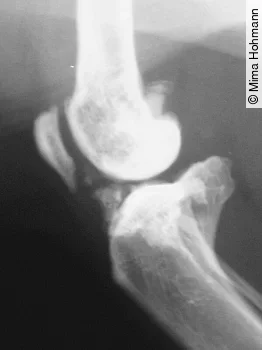

Was kann man tun? Man sollte eine ausführliche klinische Untersuchung durchführen mit Harnuntersuchung und eventuell auch einem Röntgenbild, wenn man bei der Untersuchung Schmerzen und/oder muskuläre Verspannungen an den Gelenken ([Abb. 3]), der Wirbelsäule oder im Abdomen feststellt. Dabei sollten die Gelenke auch passiv durchbewegt werden.

Osteophytäre Erkrankungen der Gelenke und der Wirbelsäule werden bei der Katze oft unterschätzt. Prävalenz der Osteoarthrose bei der Katze, dabei sind am häufigsten betroffen:

Im Alter leiden über 50 % der Katzen unter Osteoarthrose (DVG-Tagung Berlin, November 2016). Hier einige Beispiele für die Osteoarthrose bei der Katze: